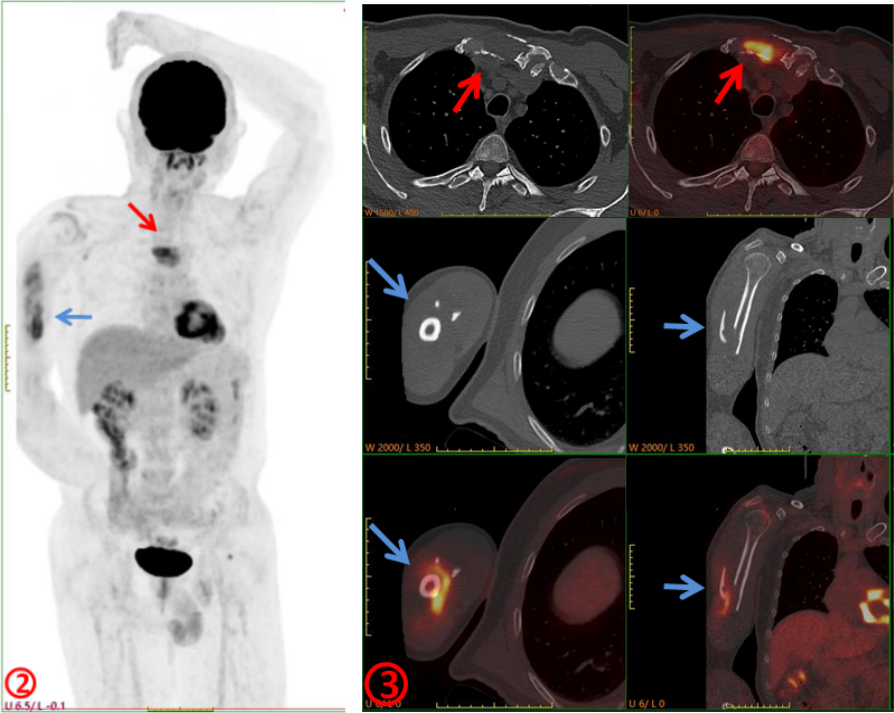

臨床初步診斷為惡性腫瘤骨轉(zhuǎn)移,遂行PET/CT進一步檢查,示右側(cè)肱骨(圖2、3,藍箭)、胸骨(圖2、3,紅箭)骨質(zhì)破壞并代謝增高,SUVmax約6.0,余未見其它明顯異常病灶,考慮骨原發(fā)腫瘤(圖2)。隨后完善胸骨病變穿刺活檢及骨髓穿刺,病理示多發(fā)性骨髓瘤。

本例患者臨床初診考慮肱骨轉(zhuǎn)移,行PET/CT檢查目的是為了查找“原發(fā)灶”,以進一步明確診斷及分期,指導(dǎo)后續(xù)治療。但PET/CT除肱骨病變外還發(fā)現(xiàn)了常規(guī)影像學(xué)沒發(fā)現(xiàn)的胸骨病變,同時未發(fā)現(xiàn)確切的原發(fā)臟器腫瘤,綜合考慮為骨原發(fā)惡性腫瘤,指導(dǎo)臨床進行穿刺活檢,最終病理證實為多發(fā)性骨髓瘤。PET/CT是功能顯像,從代謝的角度提供信息,將可疑之處點亮,讓不起眼的病灶脫穎而出;同時是全身顯像,可以“一目了然”地了解全身各臟器組織的葡萄糖代謝情況,為診斷帶來新的思路,對腫瘤臨床分期、預(yù)后評估更準確。